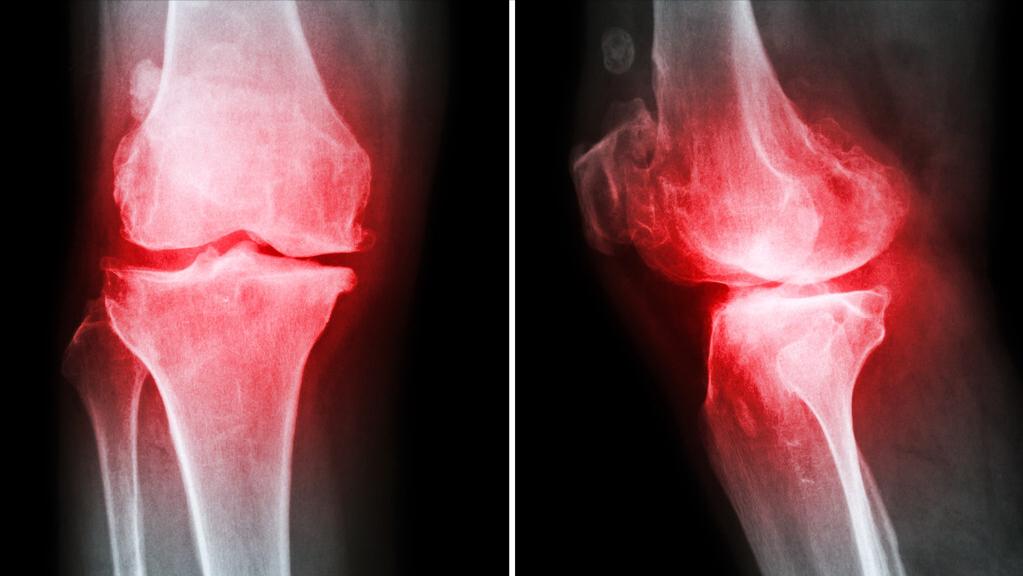

关节里面长骨刺是很多人担心的事情,以为所有的关节疼痛问题就是因为这个骨刺引起的,想着怎么把这个骨刺去掉,然后关节疼痛的问题就消失了,这样的想法可以理解,但不完全正确,请大家好好思考一下,这个长长的骨刺是一下子长出来的吗?如果关节现在开始疼痛,为什么拍片发现骨刺之前怎么就没有痛呢?有些人长了骨刺,但是关节没有疼痛又怎么解释呢?

骨刺不是导致关节疼痛的主要原因,所以长骨刺不要紧张,这是人体一个正常的退化过程,甚至可以说是人体的一个保护机制,为什么要长骨刺呢?关键的点是关节失去了原有的稳定结构,通过长骨刺来再次平衡关节的受力,使得形成再次平衡,所以长骨刺不是问题,是一个关节炎疾病的提示,如果能及时接纳这个提示,并积极进行有针对性的康复或治疗,这才是最重要的。

比如骨关节炎就是人体退化的一个重要标志,早期出现关节的问题就要重视起来,每个年龄段的关节情况是差不多的,也就是说什么年纪的人怎样的关节状况基本上是差不多,如果没有好好保护关节,那就意味着关节退变加速,最终比同龄人更早出现关节问题,当然如果能及时发现问题,并积极进行保护治疗,那么最终可以延缓退变进程,解决关节炎的问题。